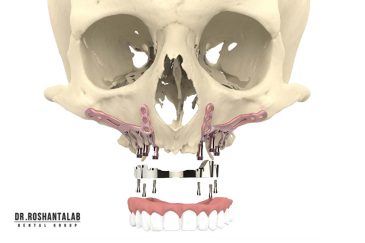

🔸جراحی پیشرفته نظیر سینوس لیفت

🔸ایمپلنت دندان با بیهوشی

انتخاب بهترین متخصص ایمپلنت که به تکنیکهای روز دنیا مسلط باشد، تضمینکننده سلامت فک و زیبایی لبخند شماست. در کلینیک دندانپزشکی دکتر روشنطلب، ما با بهرهگیری از تجهیزات دیجیتال در ۵ شعبه فعال (تهران، اصفهان، رشت و استانبول ترکیه)، خدمات تخصصی کاشت ایمپلنت دندان را برای بیمارانی که کیفیت و دقت برایشان اولویت دارد، ارائه میدهیم. در این متد، پروسه درمان با ظرافت بالا انجام شده؛ راهکاری ایدهآل برای کسانی که به دنبال درمان بدون درد با بالاترین نرخ موفقیت هستند.